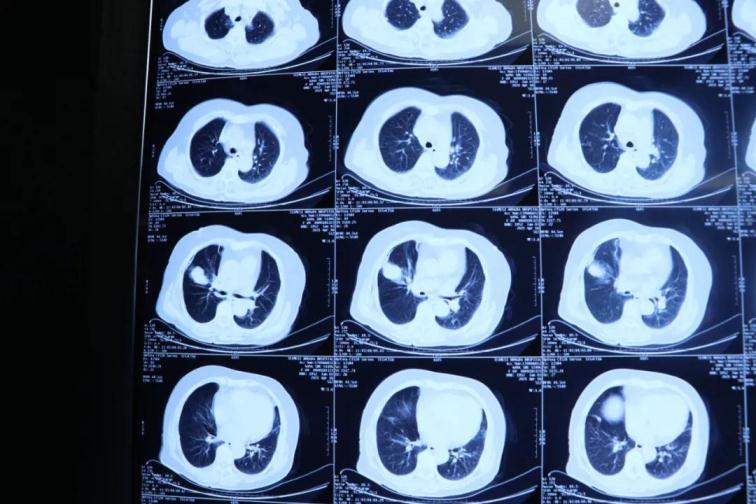

為了提高CT影像下肺腫瘤定位的精準(zhǔn)度,術(shù)前胸外科團(tuán)隊(duì)聯(lián)合CT影像科趙文禮主任和董明鑫醫(yī)師詳細(xì)研究了肺CT定位方案,采取國(guó)際上先進(jìn)的CT網(wǎng)格定位法,對(duì)肺腫瘤精確定位,定位精度可達(dá)5mm以內(nèi)。經(jīng)過團(tuán)隊(duì)合作充分準(zhǔn)備后對(duì)肺癌實(shí)施了氬氦刀穿刺治療,微創(chuàng)穿刺針孔3mm,局麻鎮(zhèn)痛,分段治療40分鐘。病人全程在韋文康護(hù)士長(zhǎng)護(hù)理團(tuán)隊(duì)心肺監(jiān)測(cè)下進(jìn)行,確保了手術(shù)安全。

氬氦刀治療后即刻CT評(píng)價(jià)肺腫瘤核心密度下降,手術(shù)后5天CT評(píng)價(jià)肺癌與周圍正常肺組織對(duì)比,水腫帶形成,癌組織出現(xiàn)壞死。治療取得了良好效果。遠(yuǎn)期效果需要繼續(xù)隨訪觀察。病人手術(shù)后1周無并發(fā)癥痊愈出院。